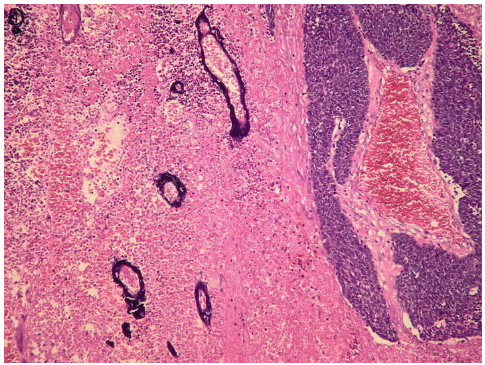

Histopathology showing the _____ effect are suggestive of a small cell carcinoma of the lung.